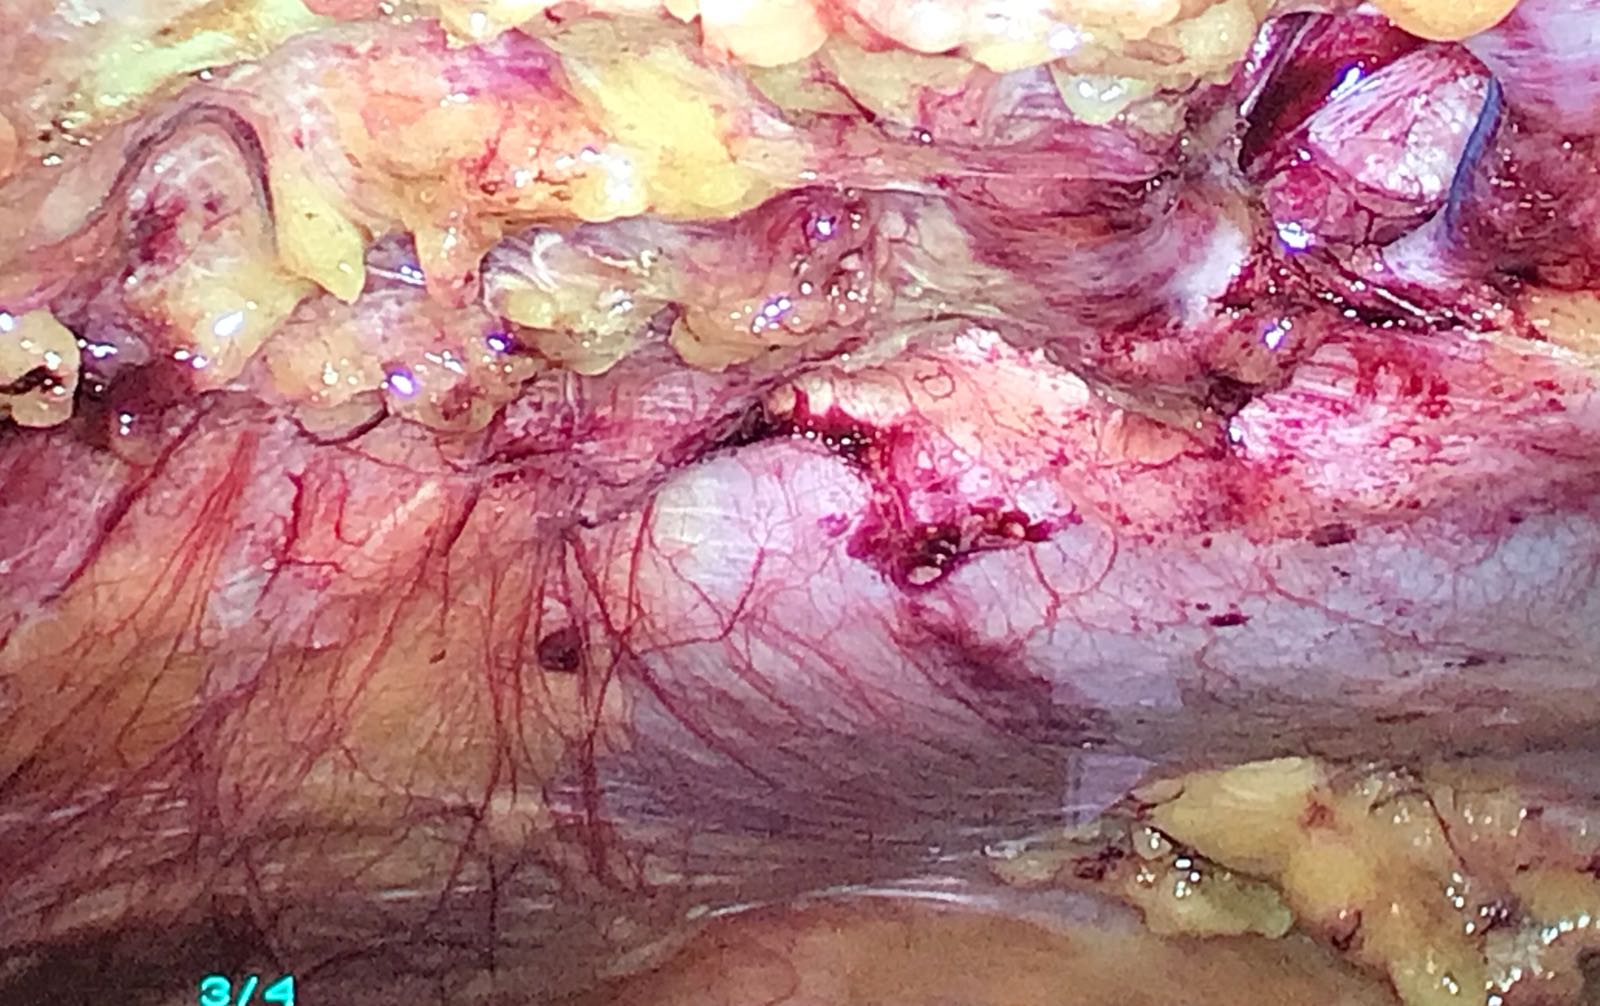

Caso Clinico » 2018-01-30-PHOTO-00000404